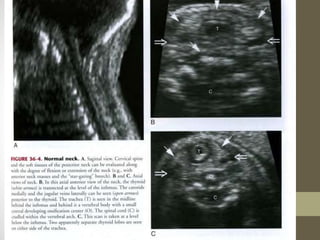

FACE AND NECK

WHAT TO SEE? IN FACE and

NECK

โ€ข 1.ORBIT

โ€ข 2.NASAL BONE

โ€ข 3.MAXILLA AND PRE MAXILLARY TRAINGLE

โ€ข 4.MANDIBLE

โ€ข 1.CYSTIC HYGROMA

โ€ข 2.OTHER SOLID OR CYSTIC MASSES